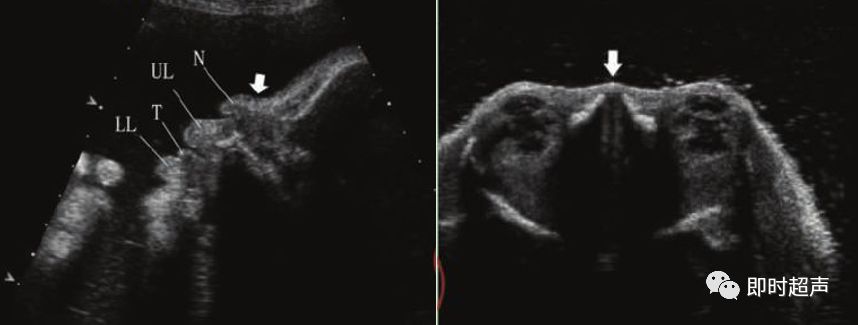

二、胎儿鼻骨(NB)

胎儿鼻骨于胚胎期第6周开始发育,9-11周通过膜性成骨方式骨化,正常胎儿中有1.4%的鼻骨存在缺失。

标准测量平面为胎儿水平位置正中矢状面,显示为鼻梁内的强回声细线。

鼻骨发育不良

NB筛查时间:11—14周,异常标准:鼻骨缺失、鼻骨短小是染色体异常的超声指标。

超声鼻骨切面:正中矢状切面和横切面诊断鼻骨缺失时,至少需要在 2 个互相垂直的切面印证。

超声检查胎儿鼻骨可作为产前超声筛查的一个有效指标。

超声检查鼻骨临床价值:11-14周胎儿鼻骨检查的成功率为95%。21-三体的胎儿60-70%鼻骨缺失,中孕期 DS 组胎儿的鼻骨缺失发生率为 55.5%,而正常对照组为0.5%。